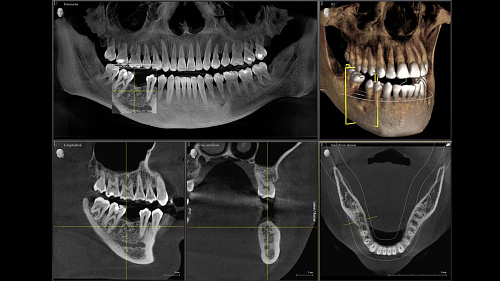

Диагностика последнего поколения, идеально решающая задачи рентгеновского обследования независимо от размеров клиники. Поля изображения зависят от определенной клинической картины, поэтому специалистам так удобно работать с ORTHOPHOS SL 3D. Данная установка делает объёмные картинки для одиночной реставрации в 3D качестве полностью всей челюсти такого размера, которого требуется.

ОБЪЁМ ДЛЯ ЛЮБЫХ ЦЕЛЕЙ

Планирование одиночной реставрации, эндодонтические исследования и пр. – для этого специалист может выбрать объёмные варианты 8 х 8 см или 11 х 10 см, также предлагается объём 5 х 5,5 см. Снимки в HD-качестве, стандартные настройки или выбор объёма обследования в зависимости от диагноза — всё это врач получает в отличном качестве, а для пациента излучение в районе исследования минимально.

С технологией SL можно за один сеанс получить огромное количество снимков. Те из них, где фокусировка наиболее чёткая, автоматически соединяются. В итоге одна процедура — снимки челюсти полностью в самом лучшем качестве. Даже нестандартные случаи не станут помехой в обследовании. К примеру, при ретинированных зубах уже после того, как снимок сделан, нужную область можно выделить подробнее, и в ещё одном рентгене необходимость отпадает.